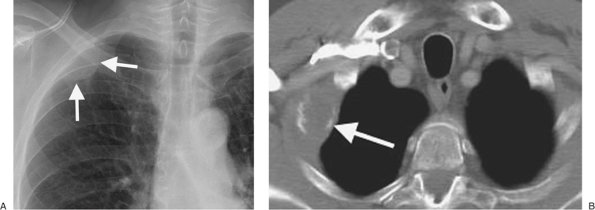

FIGURE 9-33. Lymphoma with rib involvement. A: PA chest radiograph shows a circumscribed mass (arrows) that is contiguous with the upper right lateral chest wall. B: CT shows the mass (arrow) and destruction of the right second rib.